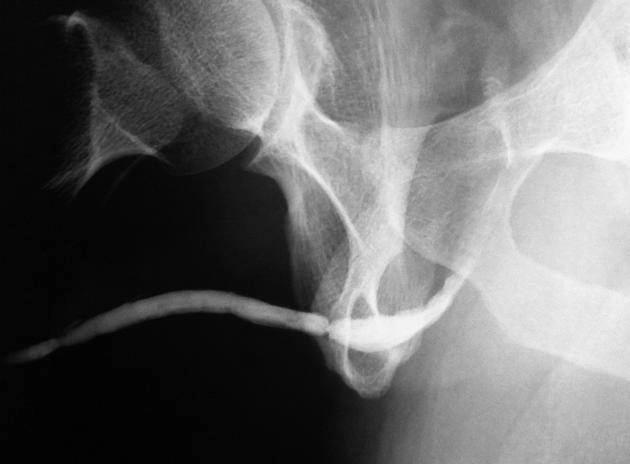

Hẹp niệu đạo (Urethral stricture)

Túi thừa niệu đạo (Urethral diverticulum)